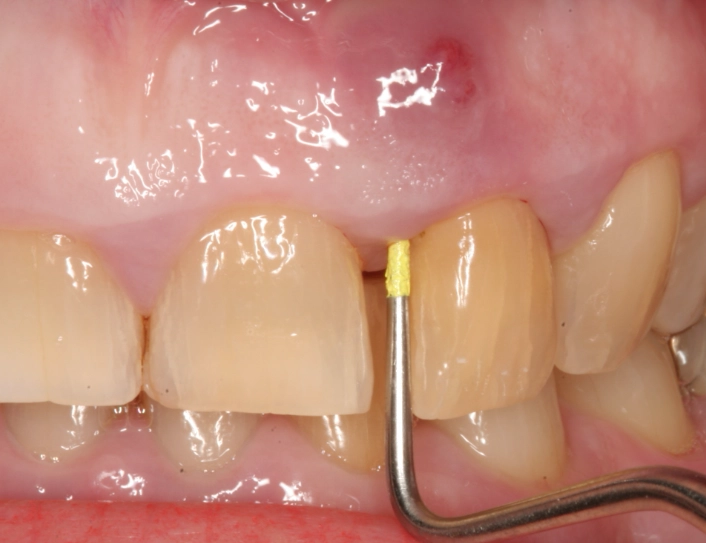

- Swelling in the Gums: Look in the mirror. Is there a pimple-like bump on the gum near the root of the painful tooth? Dentists call this a "parulis" or gum boil. It might be red, yellow at the tip, and it could ooze pus or blood if you press on it (though I don't recommend pressing on it). This is actually a drainage point for the abscess.

- Swelling in the Face or Jaw: This is when things get serious. The infection spreads from the bone into the softer tissues of your cheek, jawline, or under your tongue. The skin becomes tender, warm, and visibly puffy. The classic "chipmunk cheek" appearance.